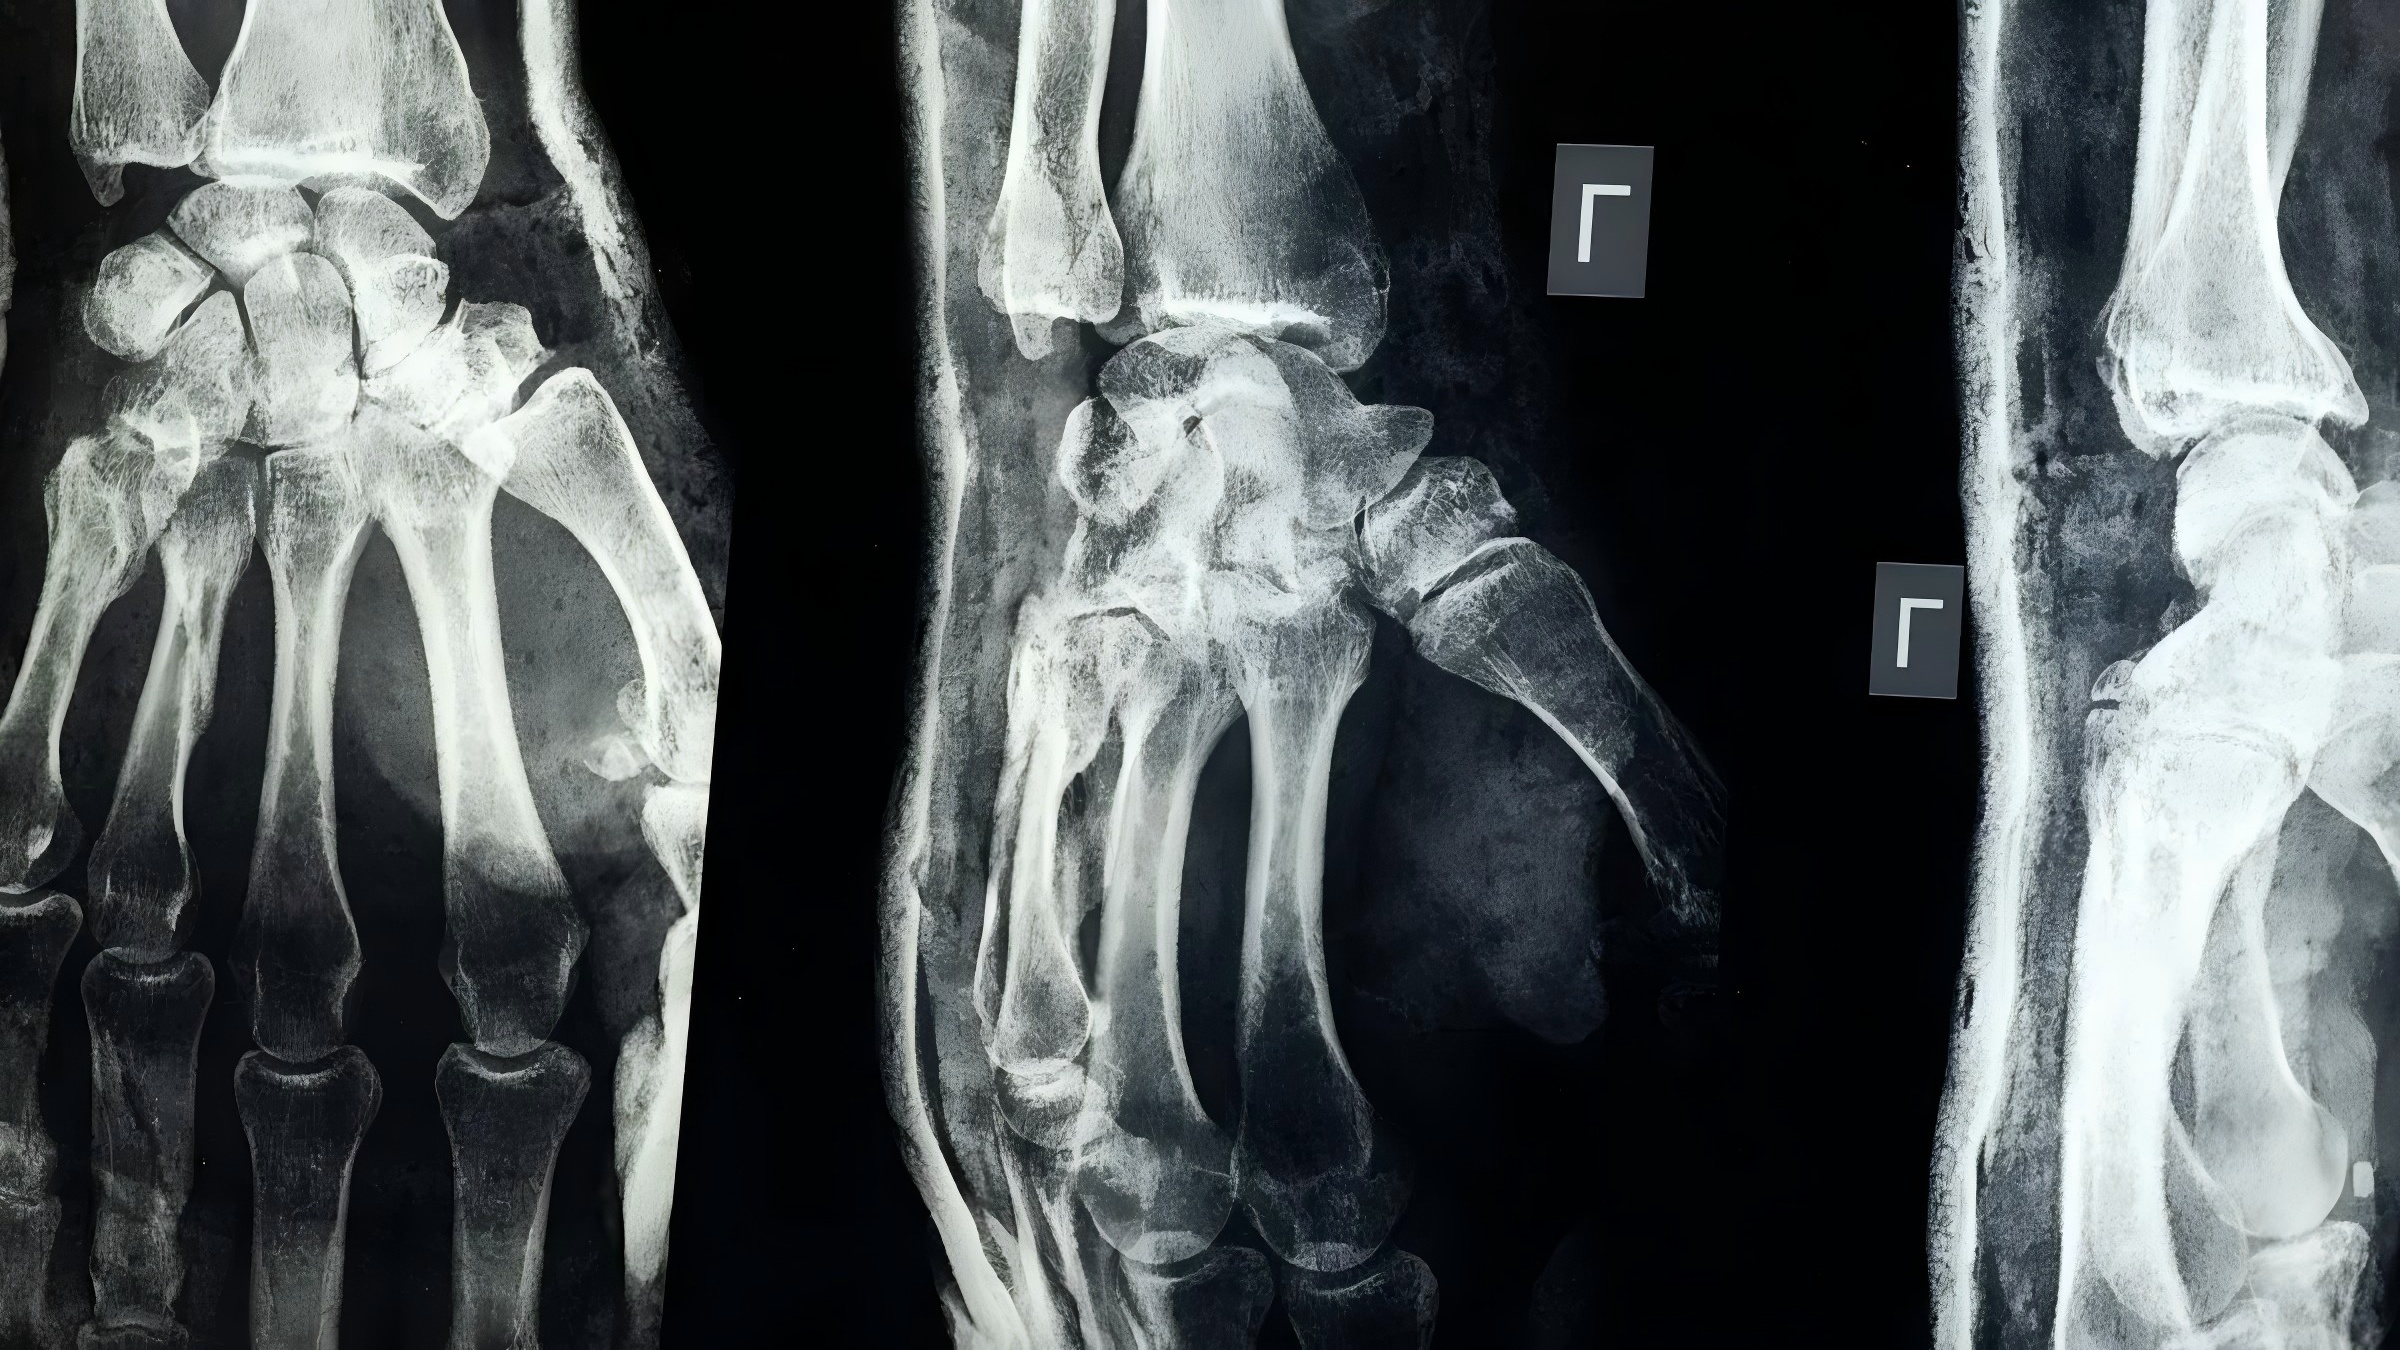

When examining X-ray images, understanding the difference between radiopaque vs. radiolucent materials is essential. Radiopaque vs. radiolucent refers to how different materials interact with X-rays: radiopaque materials block X-rays and appear white or light on the image, while radiolucent materials allow X-rays to pass through, making them look dark. The distinction between radiopaque vs. radiolucent is crucial in medical and dental imaging, as it helps healthcare professionals identify bones, teeth, cavities, and other structures. For instance, radiopaque materials are used to highlight broken bones, whereas radiolucent areas can reveal air in the lungs. The table below illustrates the differences between radiopaque vs. radiolucent materials and how each assists doctors in making accurate diagnoses:

You can use these clues to know what you see on an x-ray. Bones and metal implants are radiopaque, so they look bright white. Air spaces, like in your lungs, are radiolucent, so they look dark. Some medical implants use special polymers. Most of these polymers are radiolucent, so they do not show up well on x-rays. Scientists are trying to make these materials easier to see by adding contrast agents.

When you look at an x-ray, you need to see clear differences. Radiopaque materials block x-rays and show up bright. Radiolucent materials let x-rays pass and look dark. This contrast helps you find important details.

Radiopaque and radiolucent properties affect how well you can find problems. You use contrast to tell healthy and unhealthy tissues apart. Radiolucent areas look dark and help you find air, infections, or tumors. Radiopaque areas look light and help you see bones and fillings.

You have learned the main differences between radiopaque and radiolucent materials. Radiopaque materials, like bone or metal implants, show up white on X-rays because they stop X-rays. Radiolucent materials, such as air or soft tissue, look dark because X-rays go through them.

Radiopaque means something stops X-rays from passing through. It shows up as a white or light spot on the picture. Bones, metal implants, and dental fillings are radiopaque.

Dark spots show radiolucent materials. These let X-rays go through them. Air, soft tissue, and some plastics look dark or black on your X-ray.

Some things have both properties. For example, a dental filling can have radiopaque parts and radiolucent edges. Doctors use these differences to find problems.

Radiopaque areas make bones and devices easy to see. Radiolucent areas show air and soft tissue. Knowing these differences helps your doctor find fractures, infections, or other issues.